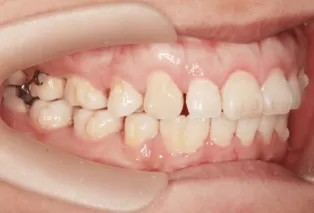

Photos intra-orales